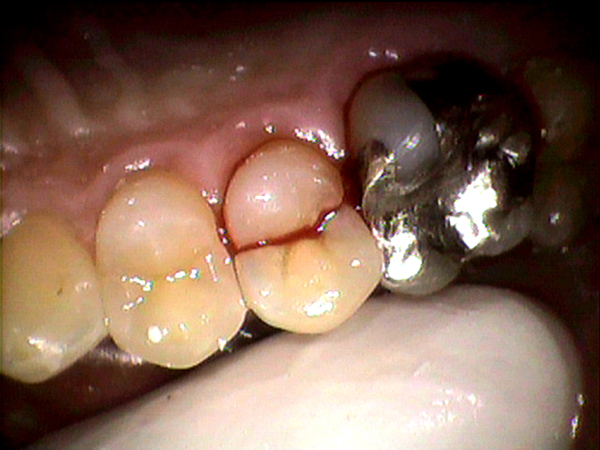

歯にヒビや亀裂が入るということをご存じない方も多く、実際にお口の中のお写真を拡大してみて頂くと驚かれます。

この患者さんも定期的に歯医者さんに行って歯石を取ってもらうなどお口の中の衛生状態は

非常に良かったのです。

しかし、噛む力に対する予防は一切しておられなかったので

このように竹割のように歯が真っ二つに割れてしまっていました。

歯は一生使い続けるものです。長く使っていると当然、消耗しヒビや亀裂が入ってきます。この写真のように歯は一晩でバキンと割れてしまうこともあります。雨垂れ石をうがつということわざ通り、小さな力であっても長年力がかかり続けることにより、大きな石であっても穴があいてしまうという意味です。